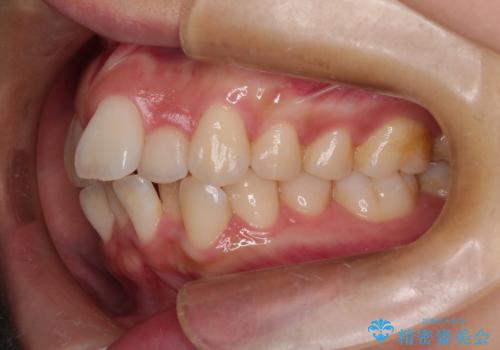

- 上下の出っ歯を気にして来院された患者様です。

口元を積極的に引っ込めるために、上下左右の第一小臼歯を4本抜歯することとしました。

下顎の正中を上顎に合わせる処置が難航し、期間が長引きました。

最終的には上下の正中も合い、横顔の印象が変わるほどスッキリとした口元となりました。